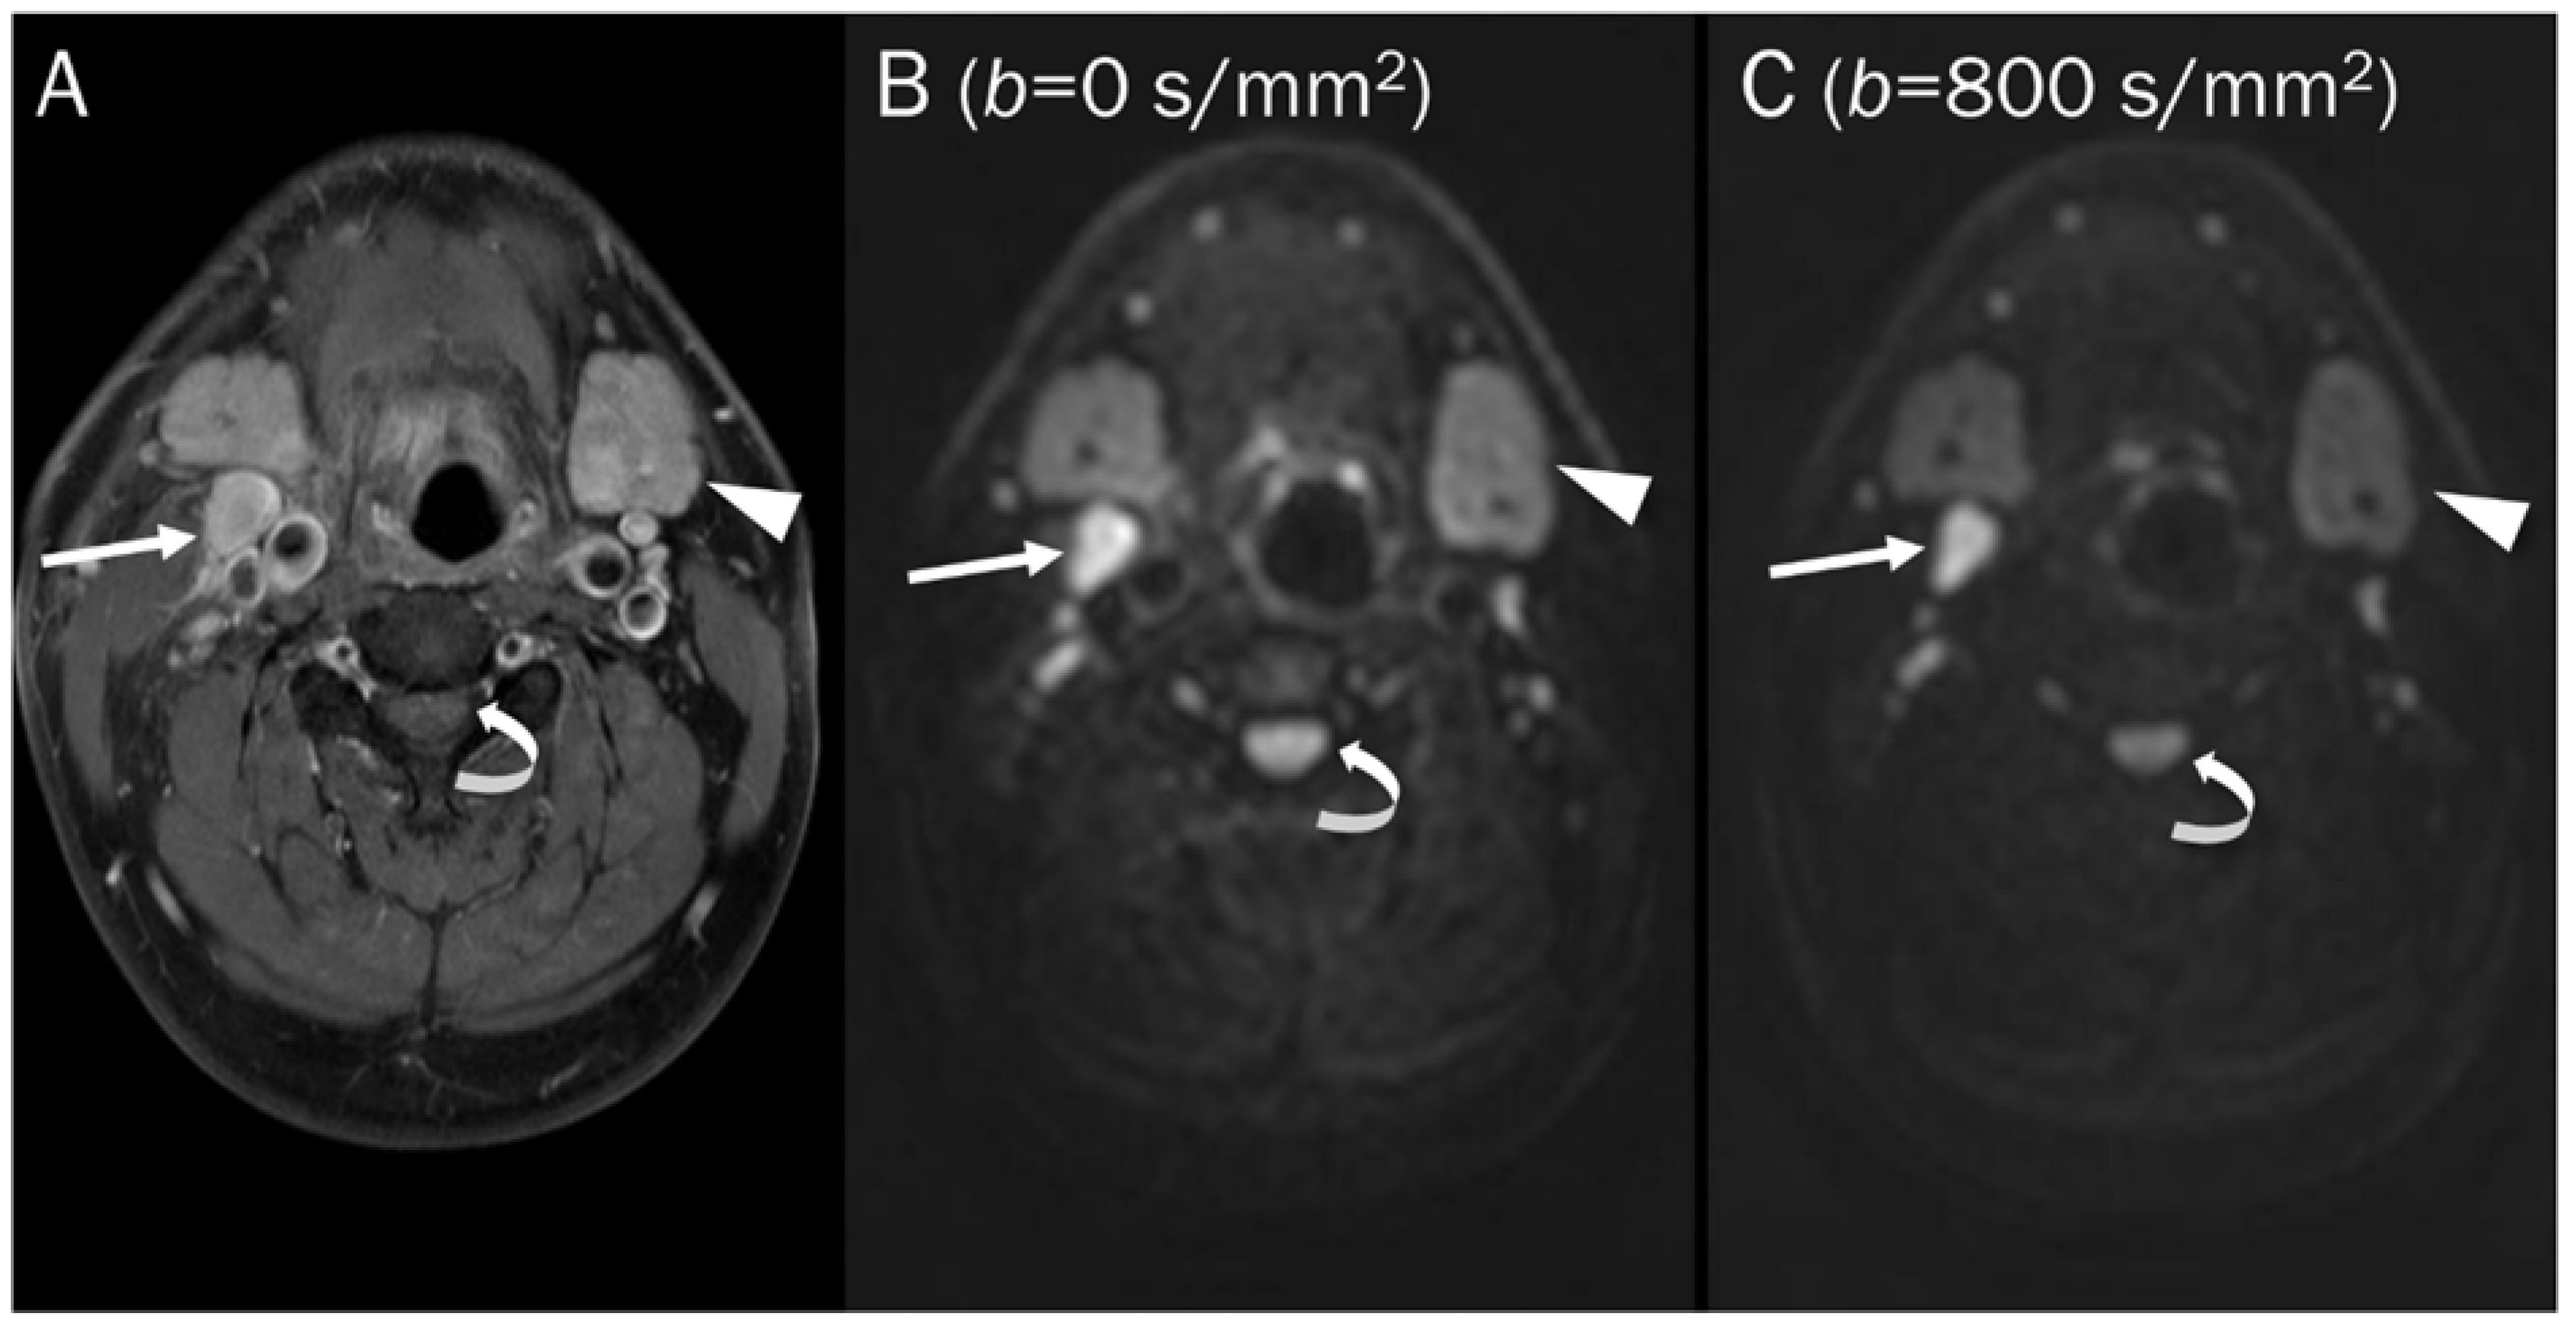

7.1. Cyst

- Subhawong, T.K.; Durand, D.J.; Thawait, G.K.; Jacobs, M.A.; Fayad, L.M. Characterization of soft tissue masses: Can quantitative diffusion weighted imaging reliably distinguish cysts from solid masses? Skelet. Radiol. 2013, 42, 1583–1592. [Google Scholar] [CrossRef]